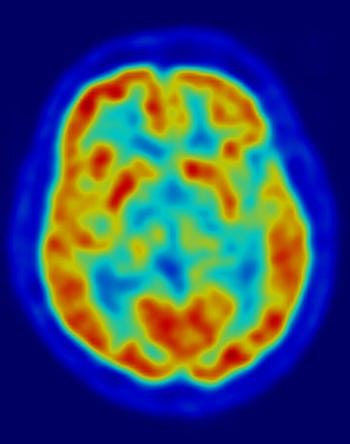

Three decades later, we know a lot more about what brains actually look like on drugs, thanks to advanced imaging techniques, curious researchers, and study participants willing to take a dose and sit in an MRI machine while they ride the high.

Last year a team of researchers published the first brain scans of people on LSD that use modern neuroimaging techniques. The results showed a surprisingly strong connection between how people experience an acid trip, and what is physically going on in their brains. Compared to a placebo group, participants on LSD had more blood flow to their visual cortex — the visual processing center — and way more connectivity between the visual cortex and the rest of the brain. The times when this activity was strongest was when people said they were experiencing visual hallucinations.

In 2014 a team of researchers published results from a study that had 19 participants dose on MDMA, then think about the happiest and worst times of their lives in an MRI machine. The brain scans that resulted showed a pretty cool pattern.

The participants repeated the experiment twice, once on MDMA and once after they ingested a placebo (they didn’t know which they had taken). But on MDMA, they rated positive memories as more vivid and emotionally intense, whereas bad memories were felt less painfully. How the participants experienced the experiment correlated nicely with what their brains actually looked like in the midst of it. When recalling happy times on MDMA, certain areas of the brain associated with emotional processing showed more activity compared with the placebo. When recalling hard times, certain brain regions showed a dulled response.